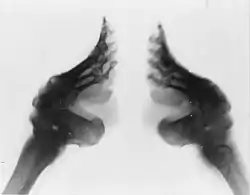

宋元明侧缠(造成腳趾骨折或變形),清折骨缠(腳底也會變形),[3]以下为折骨缠的方式:

第三階段為緊纏,要將整個腳掌的腳骨,用力扭折,使其成為彎弓拱狀。在這個階段中,腳部的肌肉己慢慢萎縮,腳背壞死的皮膚開始脫落,一段時間的出血、化膿、潰爛,壓腳下的足趾廢掉,嚴重時小腳趾會因潰爛而脫落。

最後一個階段是裹彎,費時約半年左右。這階段就是讓腳背高高隆起呈弓型,腳底則深深凹入,纏完後洼口,可達四厘米深,俗稱「折腰」,狀似拱橋。期間不僅要用纏腳布、小鞋束縛其足,還要用竹箸象打石膏一樣固定。這樣便能成為一雙「弓足」了。